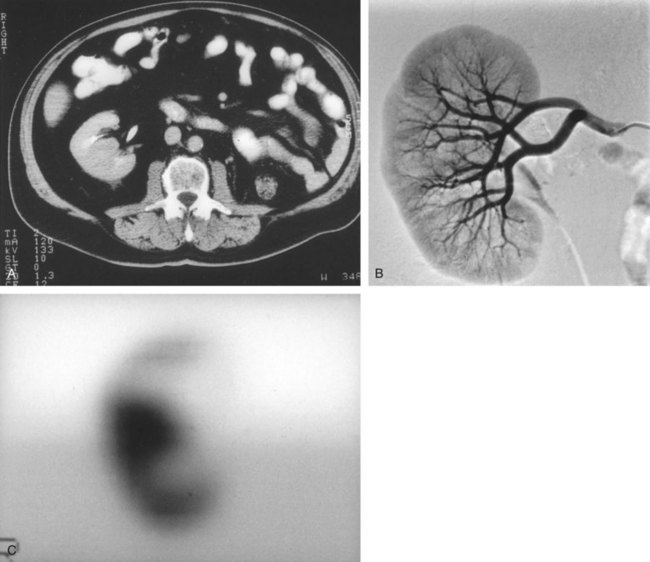

A dedicated (thin-slice) renal CT scan remains the single most important radiographic test for delineating the nature of a renal mass. CT, with and without the administration of contrast material, is necessary to take full advantage of the contrast enhancement characteristics of highly vascular renal parenchymal tumors (Davidson et al, 1997; Zagoria, 2000, Prasad et al, 2008; Ng et al, 2008; Zhang et al, 2007a). In general, any renal mass that enhances with intravenous administration of contrast material on CT by more than 15 Hounsfield units (HU) should be considered an RCC until proved otherwise (Fig. 49–2) (Hartman et al, 2004). Solid masses that also have substantial areas of negative CT attenuation numbers (below −20 HU) indicative of fat are diagnostic of AMLs (Nelson and Sanda, 2002). In 10% to 20% of solid renal masses CT findings are indeterminate, and additional testing or surgical exploration is needed to establish a definitive diagnosis. On occasion, CT demonstrates an enhancing renal segment that is isodense with the remainder of the kidney, suggestive of a renal pseudotumor. Renal pseudotumors may be due to a hypertrophied column of Bertin, renal dysmorphism, or an unusually shaped kidney (Bhatt et al, 2007). In this situation, the diagnosis of a pseudotumor can be confirmed by isotope renography with technetium-labeled dimercaptosuccinic acid or glucoheptonate (Fig. 49–3). These isotope studies demonstrate an area of increased density if the mass is a pseudotumor and an area of decreased density if the mass is a cyst or solid tumor (Israel and Bosniak, 2003a).

Figure 49–3 A, CT scan after administration of contrast material shows isodense hilar mass in solitary right kidney. B, Right renal arteriography shows no neovascularity. C, Glucoheptonate isotope renal scan shows increased density of mass indicative of hypertrophied column of Bertin.